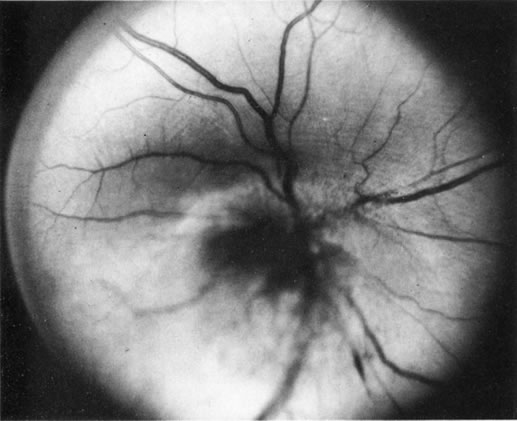

If direct ophthalmoscopy is used, a circumferential peripapillary melanoma can simulate optic neuritis (Fig. 8).

Fig. 8. A peripapillary melanoma simulating an optic neuritis. (Char DH: Clinical Ocular Oncology. 2nd ed. Philadelphia, Lippincott-Raven, 1996.)